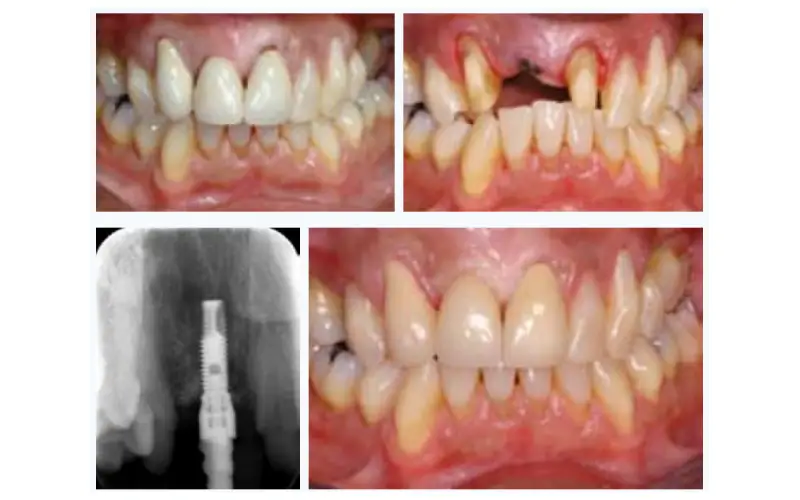

وقتی دندانی از دست میرود و ایمپلنت جایگزین نمیشود، فضای خالی باعث میشود دندانهای مجاور به سمت این فضا حرکت کنند و جابهجا شوند. این جابهجایی باعث بههمریختگی ردیف دندانها، اختلال در جویدن و مشکلات در سلامت دهان میشود. ایمپلنت با پر کردن این فضا، از حرکت غیرطبیعی دندانها جلوگیری میکند و نظم دهان را حفظ میکند.

6- کاهش تراکم و تحلیل شدید استخوان فک

نبود تحریک طبیعی ریشه دندان باعث تحلیل و کاهش تدریجی استخوان فک میشود. این فرآیند نهتنها باعث تضعیف ساختار استخوانی فک میگردد، بلکه ممکن است مشکلات جدیتری مانند تغییر شکل صورت و کاهش استحکام دندانهای باقیمانده را به همراه داشته باشد. بنابراین، عدم جایگزینی دندان با ایمپلنت به معنای از دست دادن سلامت و استحکام استخوان فک است.